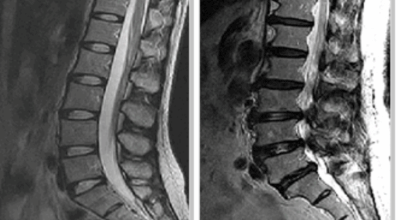

정상인 사람은 척추가 완만히 휘어져 있는데 척추관 협착증인 사람은 더 일자로 펴져 있고 정상인 사람의 척추관은 공간이 적당한데 비해 척추관척 협착증인 사람은 척추관이 일그러져 있어요. 척추관 협착증 환자는 자기 공명 영상(MRI)에서 보면 척추관 내 신경을 싸고 있는 경막 안에 정상에서 보이던 뇌척수액이 보이지 않는다는 특징이 있어요.